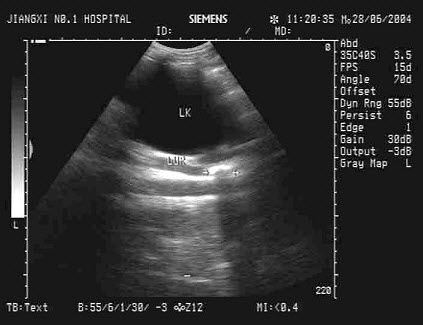

6、单项选择题

该病例最有可能诊断是()

A.左房黏液瘤

B.左房巨大血栓

C.左房恶性肿瘤

D.左房转移瘤

E.以上都不是